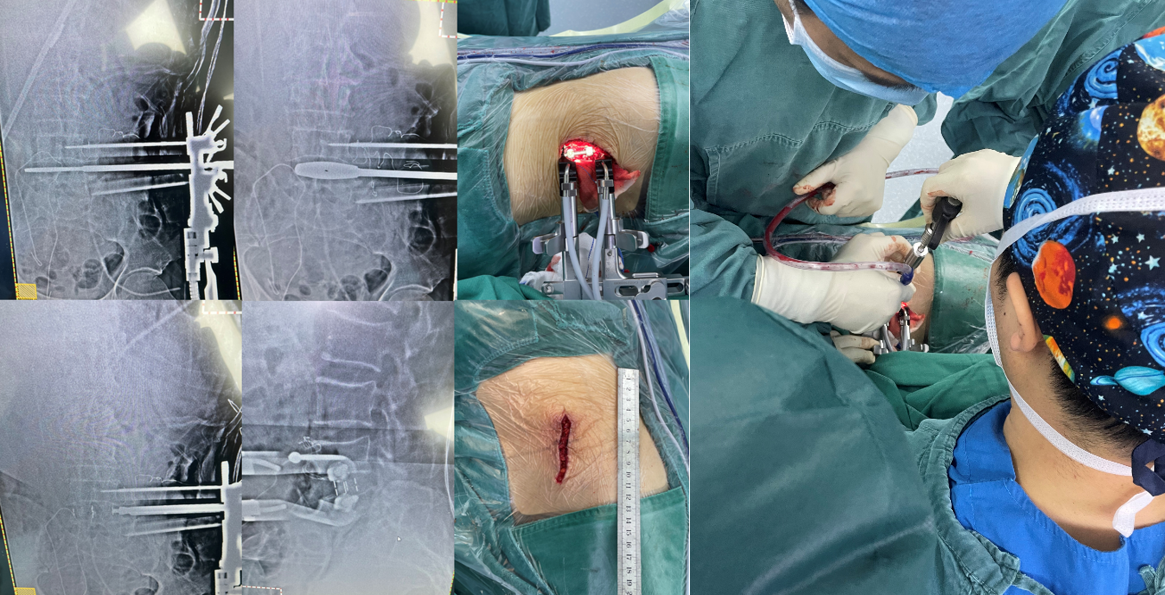

第一例患者女性,73岁,因“腰部反复疼痛20余年,加重伴左下肢疼痛4月”以“腰椎滑脱症(L3、 I°)、腰椎管狭窄症”住院。入院后经术前讨论、评估后制定治疗方案,并与患者及其家属充分沟通,行OLIF手术。术后第二天,患者下地活动,腰痛和左下肢疼痛完全消失,无明显不适,疗效满意。

术中

术后复查X线片